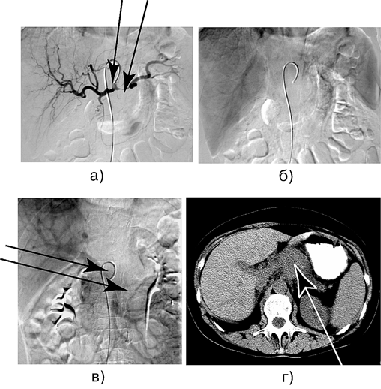

Рисунок 6. Больная Ш. Рак тела и хвоста поджелудочной железы с инвазией чревного ствола, общей печеночной артерии, селезеночной артерии, селезеночной вены и верхней брыжеечной вены:

а — целиакография: артериальная фаза, инвазия проксимального отдела общей печеночной артерии и селезеночной артерии; б — возвратная целиакоспленография, отсутствие контрастирования селезеночной вены; в — возвратная мезентерикопортография: циркулярное сужение проксимального отдела верхней брыжеечной вены; г — КТ: опухолевый узел в теле поджелудочной железы.

В дальнейшем выполнена дистальная субтотальная резекция поджелудочной железы с циркулярной резекцией чревного ствола, общей печёночной артерии, пристеночной резекцией верхней брыжеечной вены — аденокарцинома, pT4N1M0